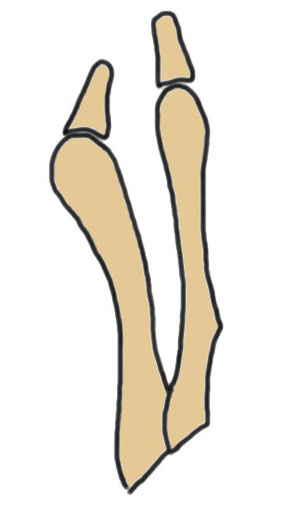

Coughlin Classification

| Type I | Type II | Type III |

|---|---|---|

| Prominent lateral condyle 5th metatarsal head | Lateral bowing of 5th metatarsal |

Increased 4/5 intermetatarsal angle Normal 5 degrees 5th metatarsal straight |

| Lateral condylectomy | Osteotomy | Osteotomy |

Lateral bowing of 5th metatarsal

Increased intermetarsal angle (IMA). Normal is 5 degrees